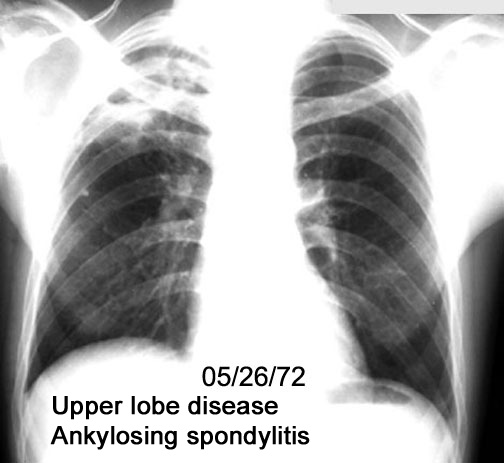

Labeled Image What are the pulmonary manifestations of Ankylosing spondylitis?